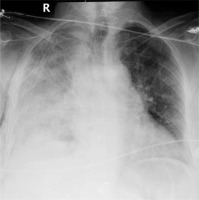

In the thoracic computed tomography of a 63-year-old female patient, a nodule with irregular margins was present in the inferior part of the upper lobe of the right lung. A transthoracic biopsy was taken from the nodule and the pathology result was reported as lung adenocarcinoma. The patient underwent right upper lobectomy and mediastinal lymph node dissection with uniportal VATS. Since the major and minor fissures were incomplete, they were intraoperatively separated with an endoscopic 60-4.8 parenchymal stapler. There was no decrease in hemoglobin value and no pathological finding on chest radiograph until postoperative day 4 (Figure 1). On postoperative day 4, the patient suddenly had hemorrhagic drainage. The patient had 500 ml of hemorrhagic drainage from the chest tube within 30 minutes. The patient was operated on in emergency conditions due to an appearance consistent with hematoma in the right hemithorax on chest radiograph (Figure 2) and decreased hemoglobin level. The uniportal VATS incision was extended posteriorly to provide access to the thorax. After the evacuation of approximately 1000 ml of hematoma, a bleeding focus was noted in the right internal mammary artery and was primarily sutured, and the bleeding was controlled. The bleeding originating from the internal mammary artery was thought to have occurred after the injury by the staple edge placed in the middle lobe to separate the minor fissure. The staple at the end was removed to prevent re-bleeding, and the area was sutured using 4-0 prolene suture. Intraoperatively, the patient received 4 units of erythrocyte suspension replacement. The hemoglobin value postoperatively reached a normal level. The patient’s postoperative chest radiographs showed expanded lungs with no pneumothorax or effusion. The patient with no pathological finding on the chest radiograph taken after the removal of the chest tube was discharged.

Figure 1

Preoperative posteroanterior chest radiograph and postoperative 4-day posteroanterior chest radiograph